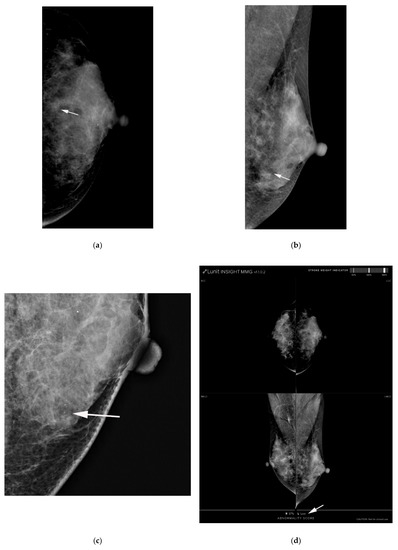

2.5. Computer-Aided Diagnosis Software

2.6. Adjustment of Radiologists’ Category Using AI-CAD Malignancy Score